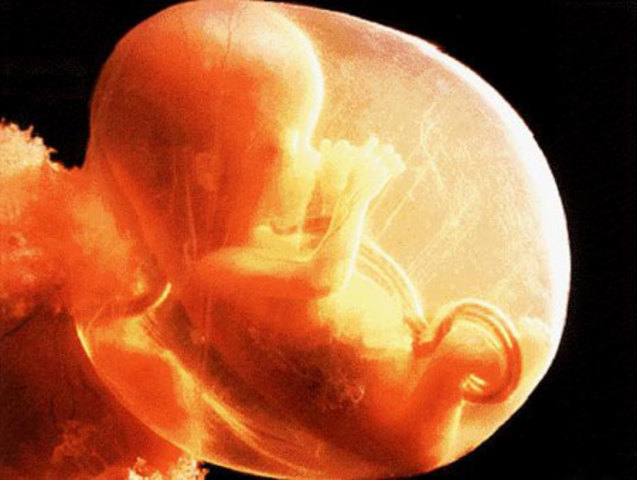

• Día 32

Día 32

Formación de la vesícula del cristalino, cúpulas ópticas y fóveas nasales

• Día 33

Día 33

Desarrollo de la lámina de la mano, seno urogenital primordial, prominencia de las fóveas nasales, evidencia de hemisferios cerebrales

• Día 44

Día 44

Aparición de los rayos digitales del pie y de las regiones de los codos, comienzo de la formación de los párpados, se distingue la punta de la nariz, presencia de pezones.

• Día 48

Día 48

Elongación y enderezamiento del tronco, comienzo de la herniación del intestino medio dentro del cordón umbilical.

• Día 51

Día 51

Flexión de los brazos a la altura de los codos, dedos diferenciados pero palmeados, aparición del prexo vascuar del cuero cabelludo, degeneración de las membranas anal y urogenital.